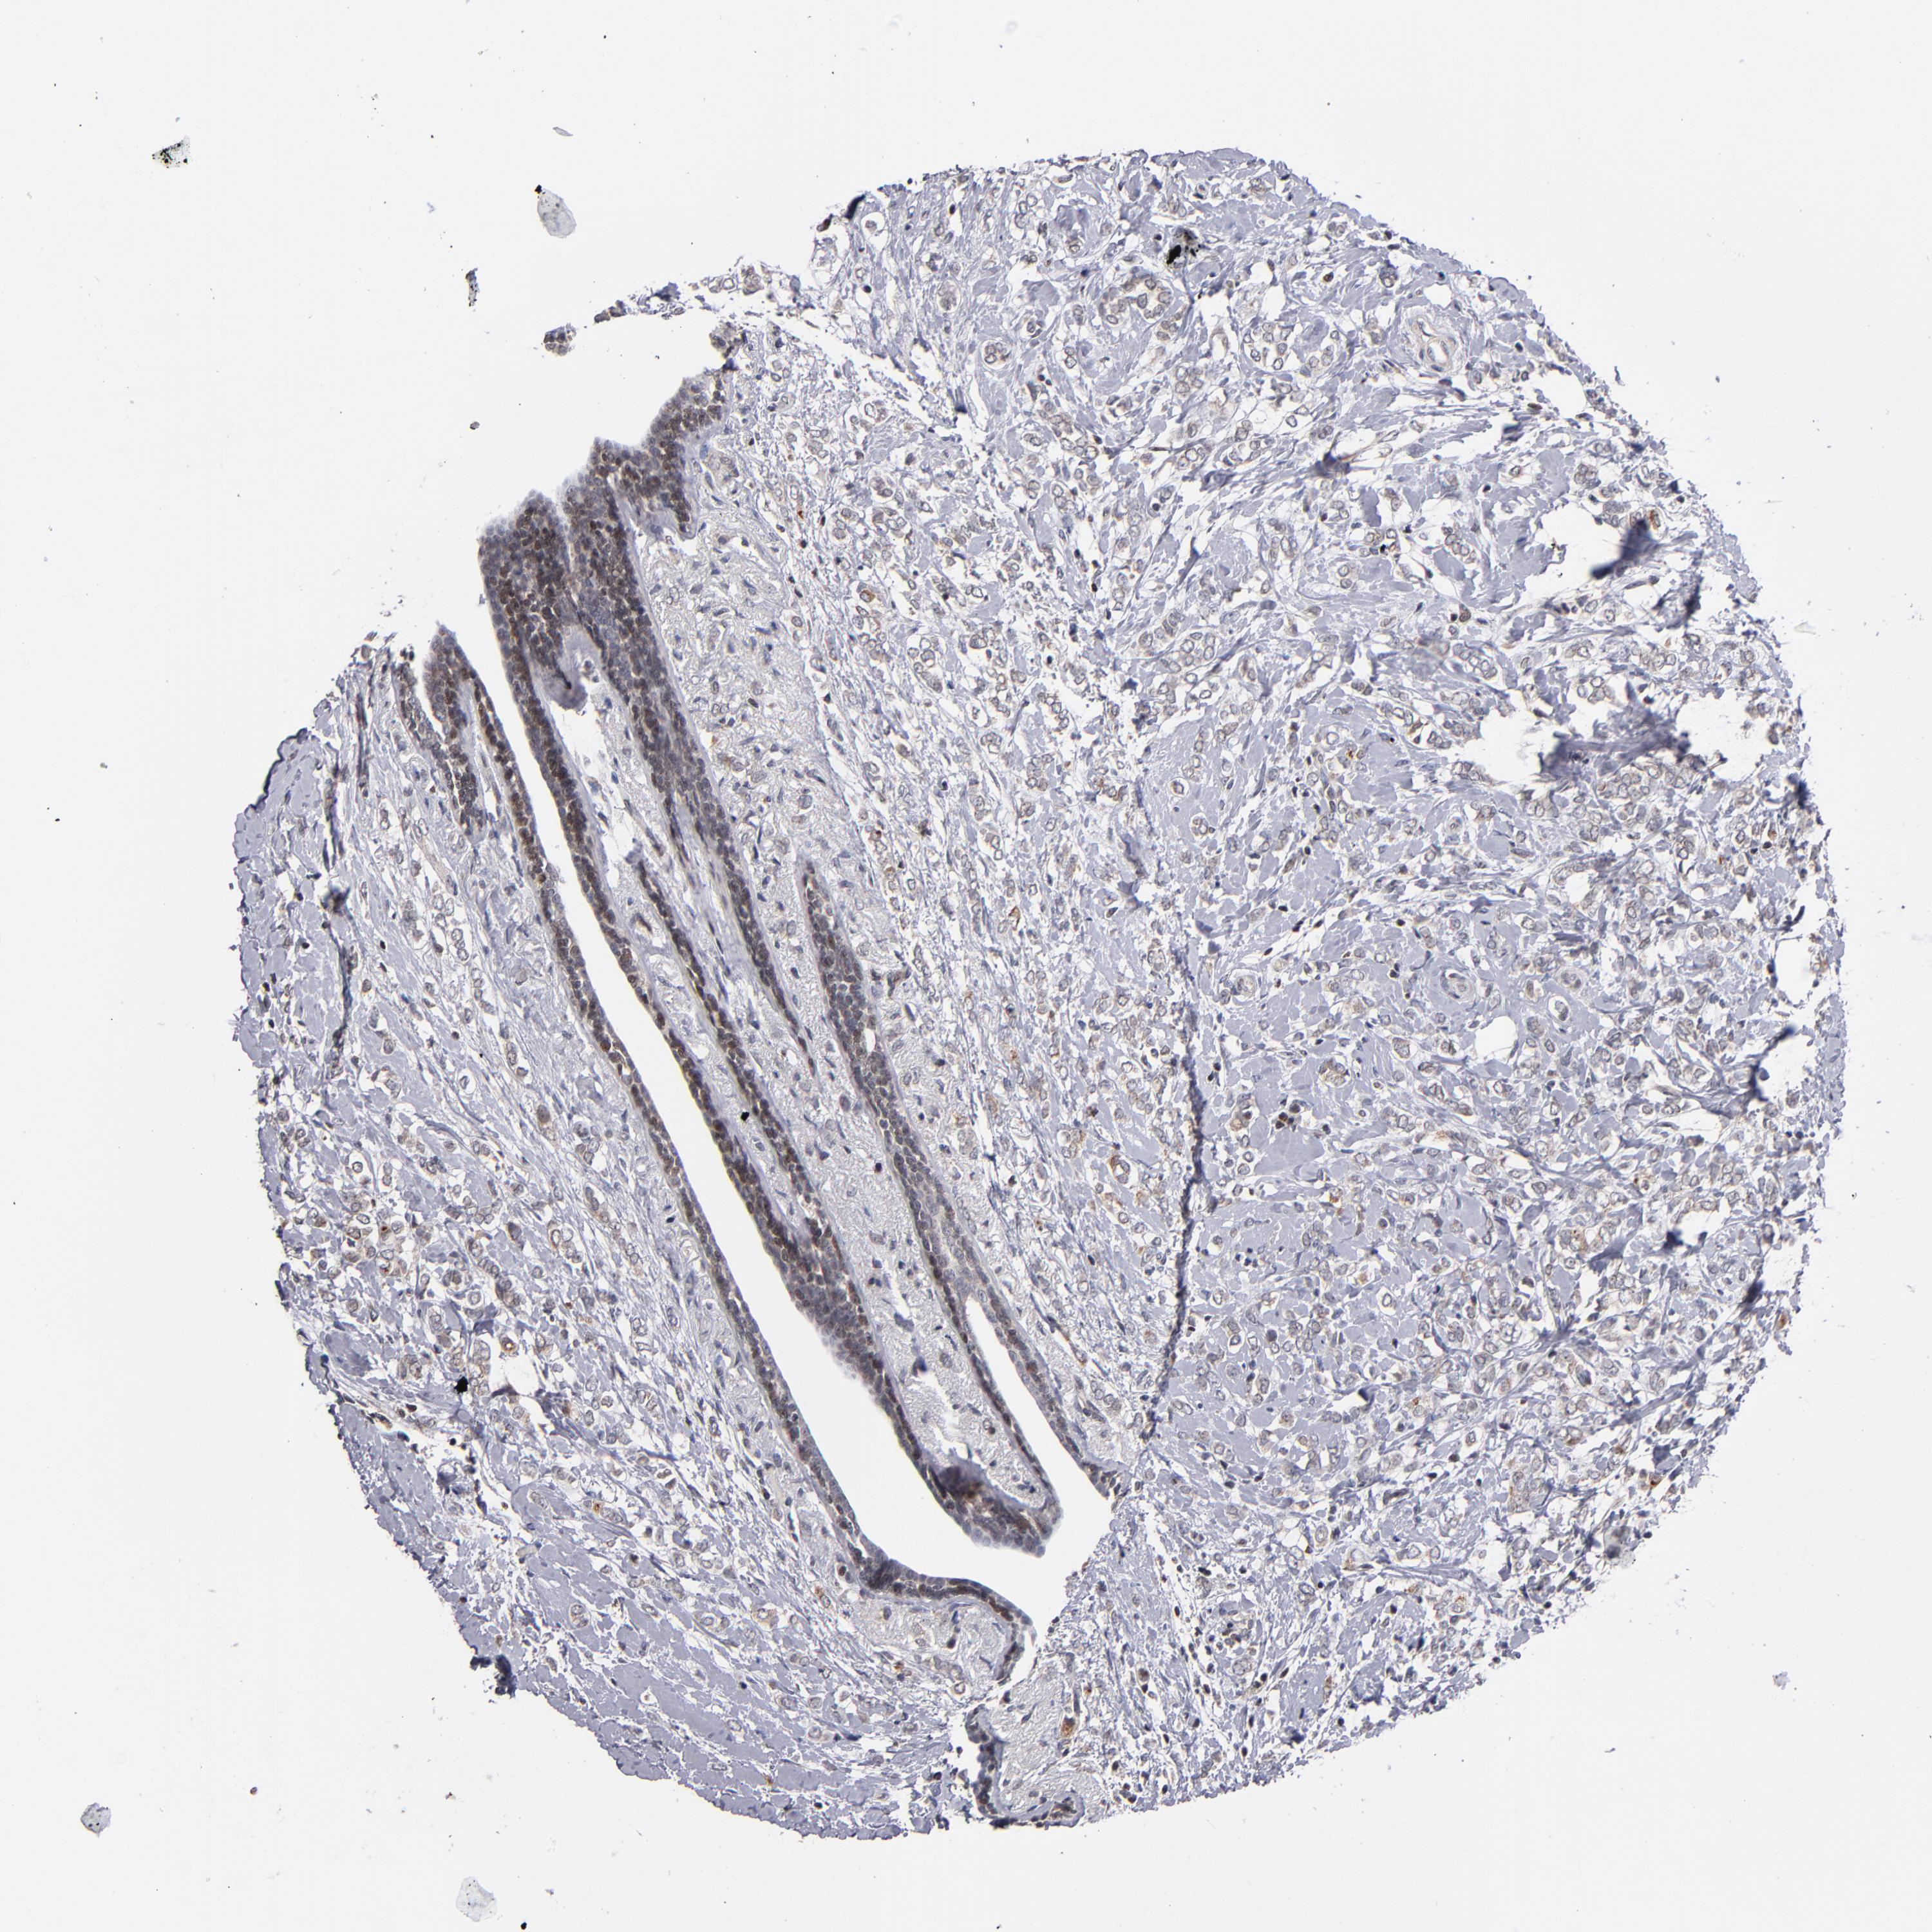

BRCA TCGA BRCA VALIDATION PROTEIN EXPRESSION

ANTIBODIES

AND

VALIDATION